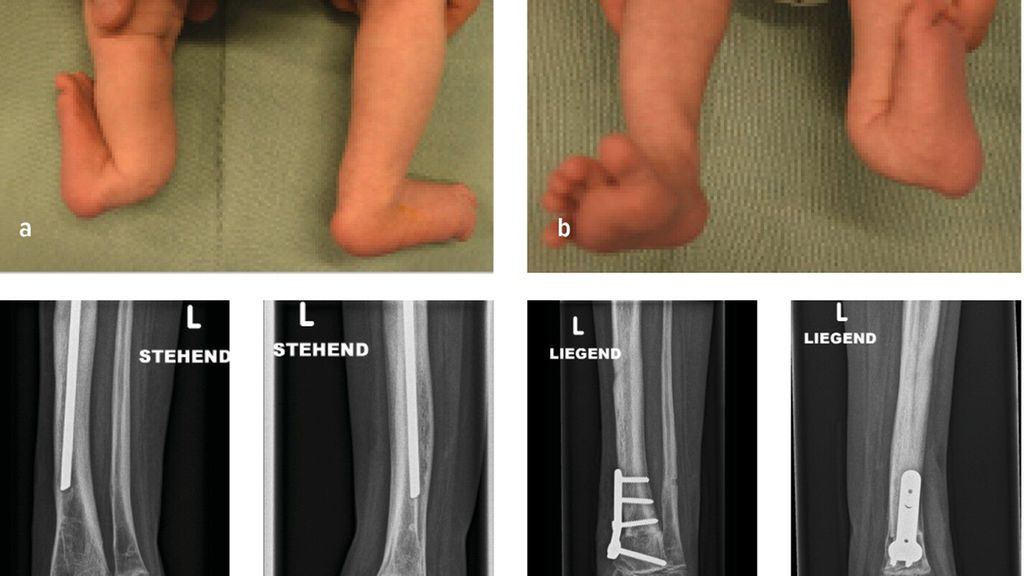

Die Biegung der Tibia richtet sich in diesem Fall nach vorne und zur Körpermitte. Diese Fehlstellung tritt vor allem bei Fibulahemimelie in unterschiedlicher Ausprägung auf. Die fibuläre Hemimelie tritt bei 1:50000 bis 1:135000 Geburten auf. Der Phänotyp der Fibulahemimelie reicht von leichter Verkürzung bis zu einem Fehlen der Fibula und führt dadurch zu einem typischen anterioren oder anteromedialen Bowing des Unterschenkels. Instabilitäten des Knie- und Sprunggelenkes können mit der Fibulahemimelie einhergehen.1,2 Fußfehlbildungen gekennzeichnet durch das Fehlen der lateralen Strahlen, Koalitionen, Equinovalgus- oder Klumpfußstellung können auftreten. Anschaulich illustriert wird dieses Zustandsbild durch den klinischen Fall eines 6-jährigen Patienten mit unilateraler FH und 4-strahligem Fuß rechts sowie einer ausgeprägten Beinlängendifferenz vor chirurgischer Rekonstruktion. (Abb.1a–c).3 Die sporadische Form ist meistens unilateral und kann mit einem kongenitalen Femurdefekt einhergehen.1,4 Bilaterale Formen sind selten und treten häufiger im Rahmen von Syndromen auf. Eine Disruption in der frühen Embryogenese wird als wahrscheinlichste Ursache einer Fibulahemimelie angesehen, die Ätiologie ist jedoch unklar.1 Die am häufigsten verwendete Klassifikation nach Achterman-Kalamchi unterteilt die Fibulahemimelie in lediglich zwei Typen mit einer Subgruppe:5

Abb. 1: 6-Jähriger mit unilateraler FH und 4-strahligem Fuß rechts sowie ausgeprägter Beinlängendifferenz vor chirurgischer Rekonstruktion (a–c). Laufende Valguskorrektur und Beinlängenausgleich mittels externen hexapoden Fixateurs mit Fußeinschluss

Die neuere Unterteilung nach Paley bezieht die Sprunggelenkspathologien in die Klassifikation mit ein (vier Typen mit Untergruppen) und gibt auch hier Empfehlung zu operativen Verfahren ab.1 Ziele der chirurgischen Rekonstruktion umfassen die Fußkorrektur mit plantigrader Position, den Ausgleich der Beinlängendifferenz bei Wachstumsabschluss sowie eine neutrale Beinachse. Neben konservativen Maßnahmen wie Schuhzurichtungen und Orthosenversorgung, erfolgt die Korrektur schließlich über chirurgische Verfahren wie Stabilisierungstechniken des Knie- und Sprunggelenkes, Wachstumslenkung sowie beinverlängernde Maßnahmen. Im Fall des 6-jährigen Patienten erfolgten eine Valguskorrektur und ein Beinlängenausgleich mittels externen hexapoden Fixateurs und Fußeinschluss (Abb.1d,e).6 In besonders schweren Fällen mit ausgeprägter Fehlbildung und Hypoplasie des Fußes kann eine Amputation mit anschließender Orthoprothesenversorgung in Betracht gezogen werden.7